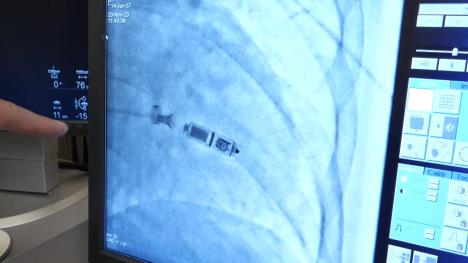

Televizija Kurir prisustvovala je ugradnji minijaturnog pejsmejkera, u operacionoj sali Univerzitetskog kliničkog centra Niš! Ovaj mikro pejsmejker se ugrađuje direktno unutar srčanog mišića kroz femoralnu venu i naročito je važan za pacijente kod kojih klasična operacija nosi veliki rizik

Taj mikro pejsemejker ugrađuje se, kažu, direktno unutar srčanog mišića, kroz femoralnu venu, i posebno je važan za pacijente kod kojih klasična operacija nosi veliki rizik.

Bez klasičnog operativnog reza, ovaj metod donosi velike benefite pacijentima koji su podložni riziku prilikom ugradnje klasičnog pacemakera. Smanjuje se trauma, a rizik od infekcije džepa u koji se aparat ugrađuje je takođe manji. Ovo je kratko definisana intervencija ugradnje minijaturnog pacemakera, koja se uspešno izvodi u Nišu u poslednje vreme.